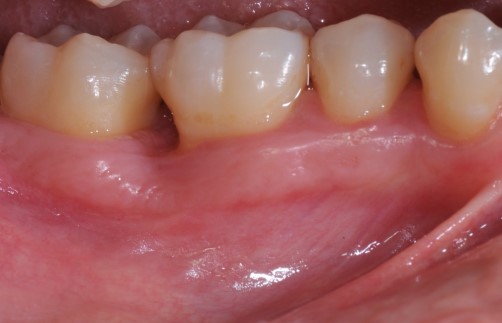

Radiographic view before periodontal regenerative therapy with Straumann® Emdogain®. A deep intrabony defect appeared mesially and distally on the left mandibular first premolar. Pre-surgical probing measured 8 mm. The defect morphology presented as well-contained.